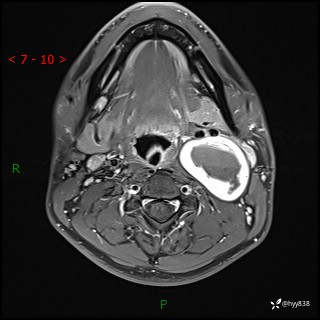

现病史:患者约3年前因感冒发现左侧颈部长一肿物,约半个鸡蛋大小,无明显疼痛及其他不适,一直未行特殊处理。3个月前发现左侧颈部肿物变大,随后至当地市第二人民医院耳鼻喉科行左侧颈部彩超示:左侧颈部囊实混合性包块;喉部MPR示:左侧胸锁乳突肌内前方占位,累及左侧喉旁间隙,建议增强扫描。建议手术治疗。患者考虑。随后至我院肿瘤科就诊,行细胞学穿刺示:考虑血管源性肿瘤可能,建议进一步检查。建议至我院口腔科就诊,行颌面部MRI示:左侧颌下腺后方团状异常信号灶,建议增强。建议手术治疗。为求进一步治疗,门诊以“左侧颈部肿物”收入院。 起病以来,患者神志清、精神良好,饮食睡眠良好,大小便正常,体重未见明显变化。

颈部MRI平扫+增强